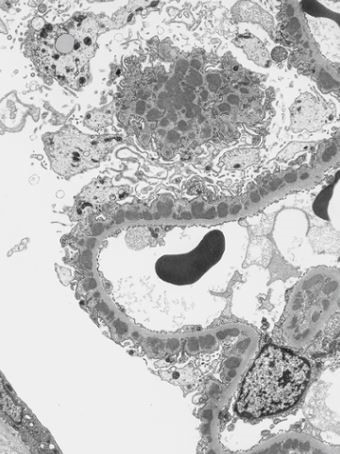

What is this and why?

This is a comparison of normal glomeruli and podocyte foot process effacement in MCD and FSGS